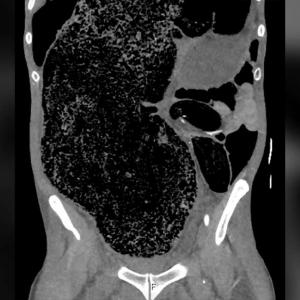

В конкретния скорошен случай 25-годишна жена отива в спешното на болница в Чандигар, Индия с кървави сълзи на лице. Това е вторият път, в който проявява този симптом, като първоначалната му поява е била преди месец. И в двата случая – кървавите сълзи се появяват, докато е в менструация.

Източник: BMJ Case Reports 2021.

Лекарите извършват множество тестове, за да установят причината. Резултатите от всички са нормални. По очите не са открити наранявания, никой от семейството не страда от това състояние, а кръвоносните съдове в конюктивата не са подути или пълни с кръв. Гинеколог и специалист уши, нос, гърло също я преглеждат и не откриват нищо. Жената е хемодинамично стабилна с нормално очно налягане. Не е открито кървене от която и да е друга област в тялото, а тестовете за крехкост са отрицателни, а нивата на факторите, свързани с кръвосъсирването, са нормални. Конюнктивалната проба също е нормална – не са открити анормални клетки.